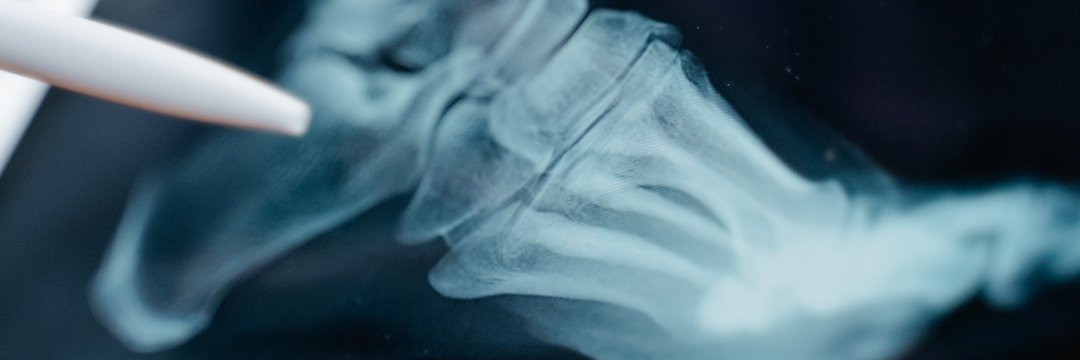

Most people ignore joint pain or stiffness at first. It feels minor – maybe just fatigue, bad posture, or a long day. But sometimes, these small signals are the body’s way of pointing toward something deeper. Before getting into symptoms, it helps to understand what is orthopedic care. In simple terms, orthopedics is the branch of medicine that deals with bones, joints, muscles, ligaments, and overall movement of the body.

To better recognize early signs, you should first know what falls under orthopedic care. If you’ve ever wondered who is orthopedist, the answer is straightforward – an orthopedist is a doctor who specializes in diagnosing and treating conditions related to the musculoskeletal system.

This includes everything from minor sprains to chronic joint disorders and fractures. These specialists don’t just treat injuries; they also help manage long-term conditions like arthritis, back pain, and ligament issues.